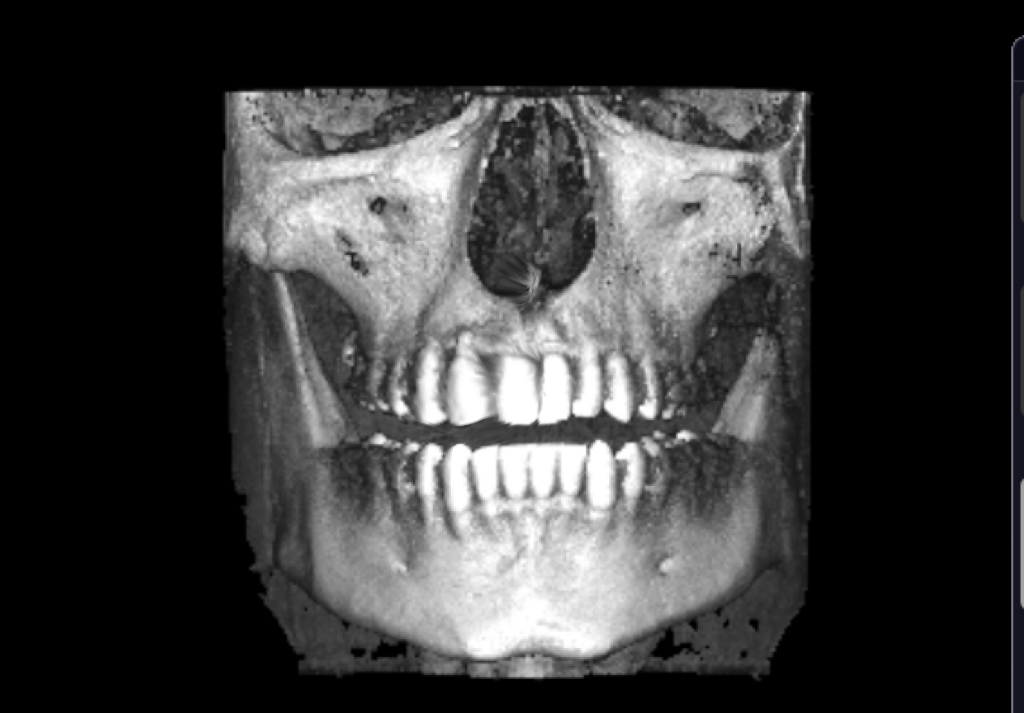

Mandibular deviation so skeletal

The chin is actually in line with the center of the skull

I was judging of this pic, looked like there was mandibular deviation

seems to be centered, it's just the alveolar bone playing tricks with you head, your teeth are a lil overcrowded and the "midline" in the teeth has "shifted" (thankfully because of the xray you can see that with braces a clear aligner or even a toothborne expander you could fix your overcrowded lower teeth and move the "mid-line" to the right spot, your occlusion doesn't follow the "guide lines" of the bones also I notice that the upper jaw seems to be inlign with the "midline"(teeth and the base of the nasal cavity as you can see in the image)

The alveolar bone in the upper jaw seems to be shifted